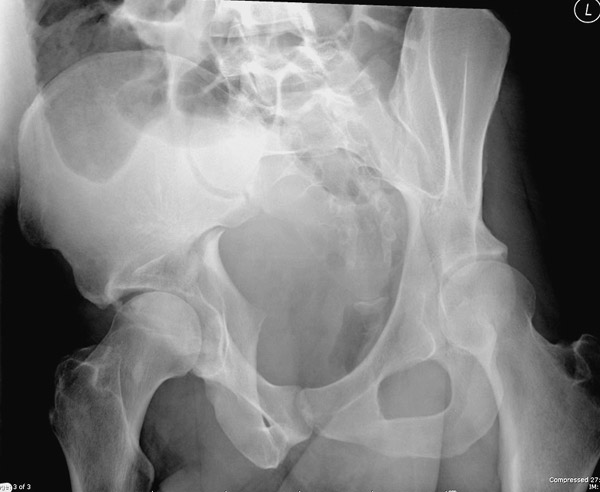

Повторная операция – реостеосинтез костей таза была проведена через 1 месяц после первичной. Дз: задний вывих правого бедра (сроки -3 месяца). Асептический некроз головки правой бедренной кости. Неконсолидирующийся перелом средней трети правой бедренной кости, неправильно консолидирующийся перелом лодыжек правой голени с подвывихом стопы кзади, передняя медиальная нестабильность правого К/С. Сгибательно-приводящая контрактура правого Т/Б сустава, сгибательно-разгибательная контрактура правого К/С, эквинусная установка в правой стопе на фоне пост-операционного пареза

Перелом вертлужной впадины отличается от “переломов таза” не только исследованием, но также тактикой. По классификации Летурнеля расположение линии перелома характерно для поперечного перелома вертлужной впадины, но наличие шурупов в заднем крае (второй снимок) и вывих бедра подтверждают, что здесь сочетание заднего края с поперечным переломом.

Надо сделать снимки Judet и при возможности КТ. А 3Д снимки покажут общий вид, но детали в области суставов дает срезы КТ.

В большинстве вывих происходит при переломах задней стенки, а без хорошей фиксации головку невозможно удержать! Про осложнения можно говорить еще, но навряд ли Вам интересно отдуваться за чужой грех. И если Вы не из WikiLeak, который сливает чужие осложнения, а ваше желание помочь искреннее, тогда надо организовать необходимые снимки и исследовании. Возможно, не все потеряно и какой-нибудь ближайщий центр протянет руки помощи....